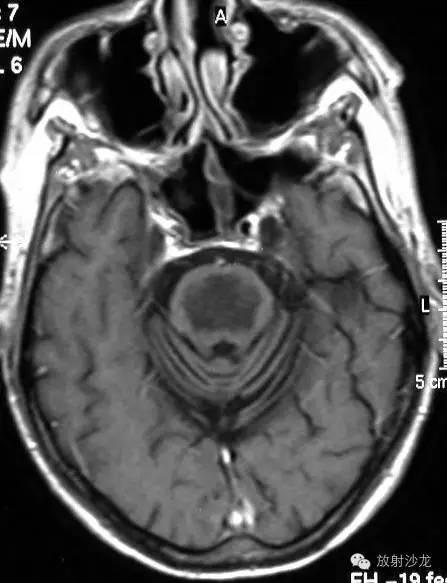

5.2影像学:CT平扫示桥脑基底部低密度区,无占位效应,一般不侵犯中脑和向后侵犯中央纤维束。病灶常累及前额叶,偶可累及外侧基底节、丘脑、大脑皮层下白质;增强扫描病灶无强化。MRI平扫示急性期患者桥脑上部中央出现三角形、或对称性圆形、卵圆形T1加权像低信号,T2加权像高信号的病灶,增强扫描有显著异常强化;不累及脑 室周围白质区,但大脑皮层下白质、半卵圆中心、胼胝体、丘脑、纹状体、中脑和小脑可见散在异常信号病灶。MRI为本病首选。